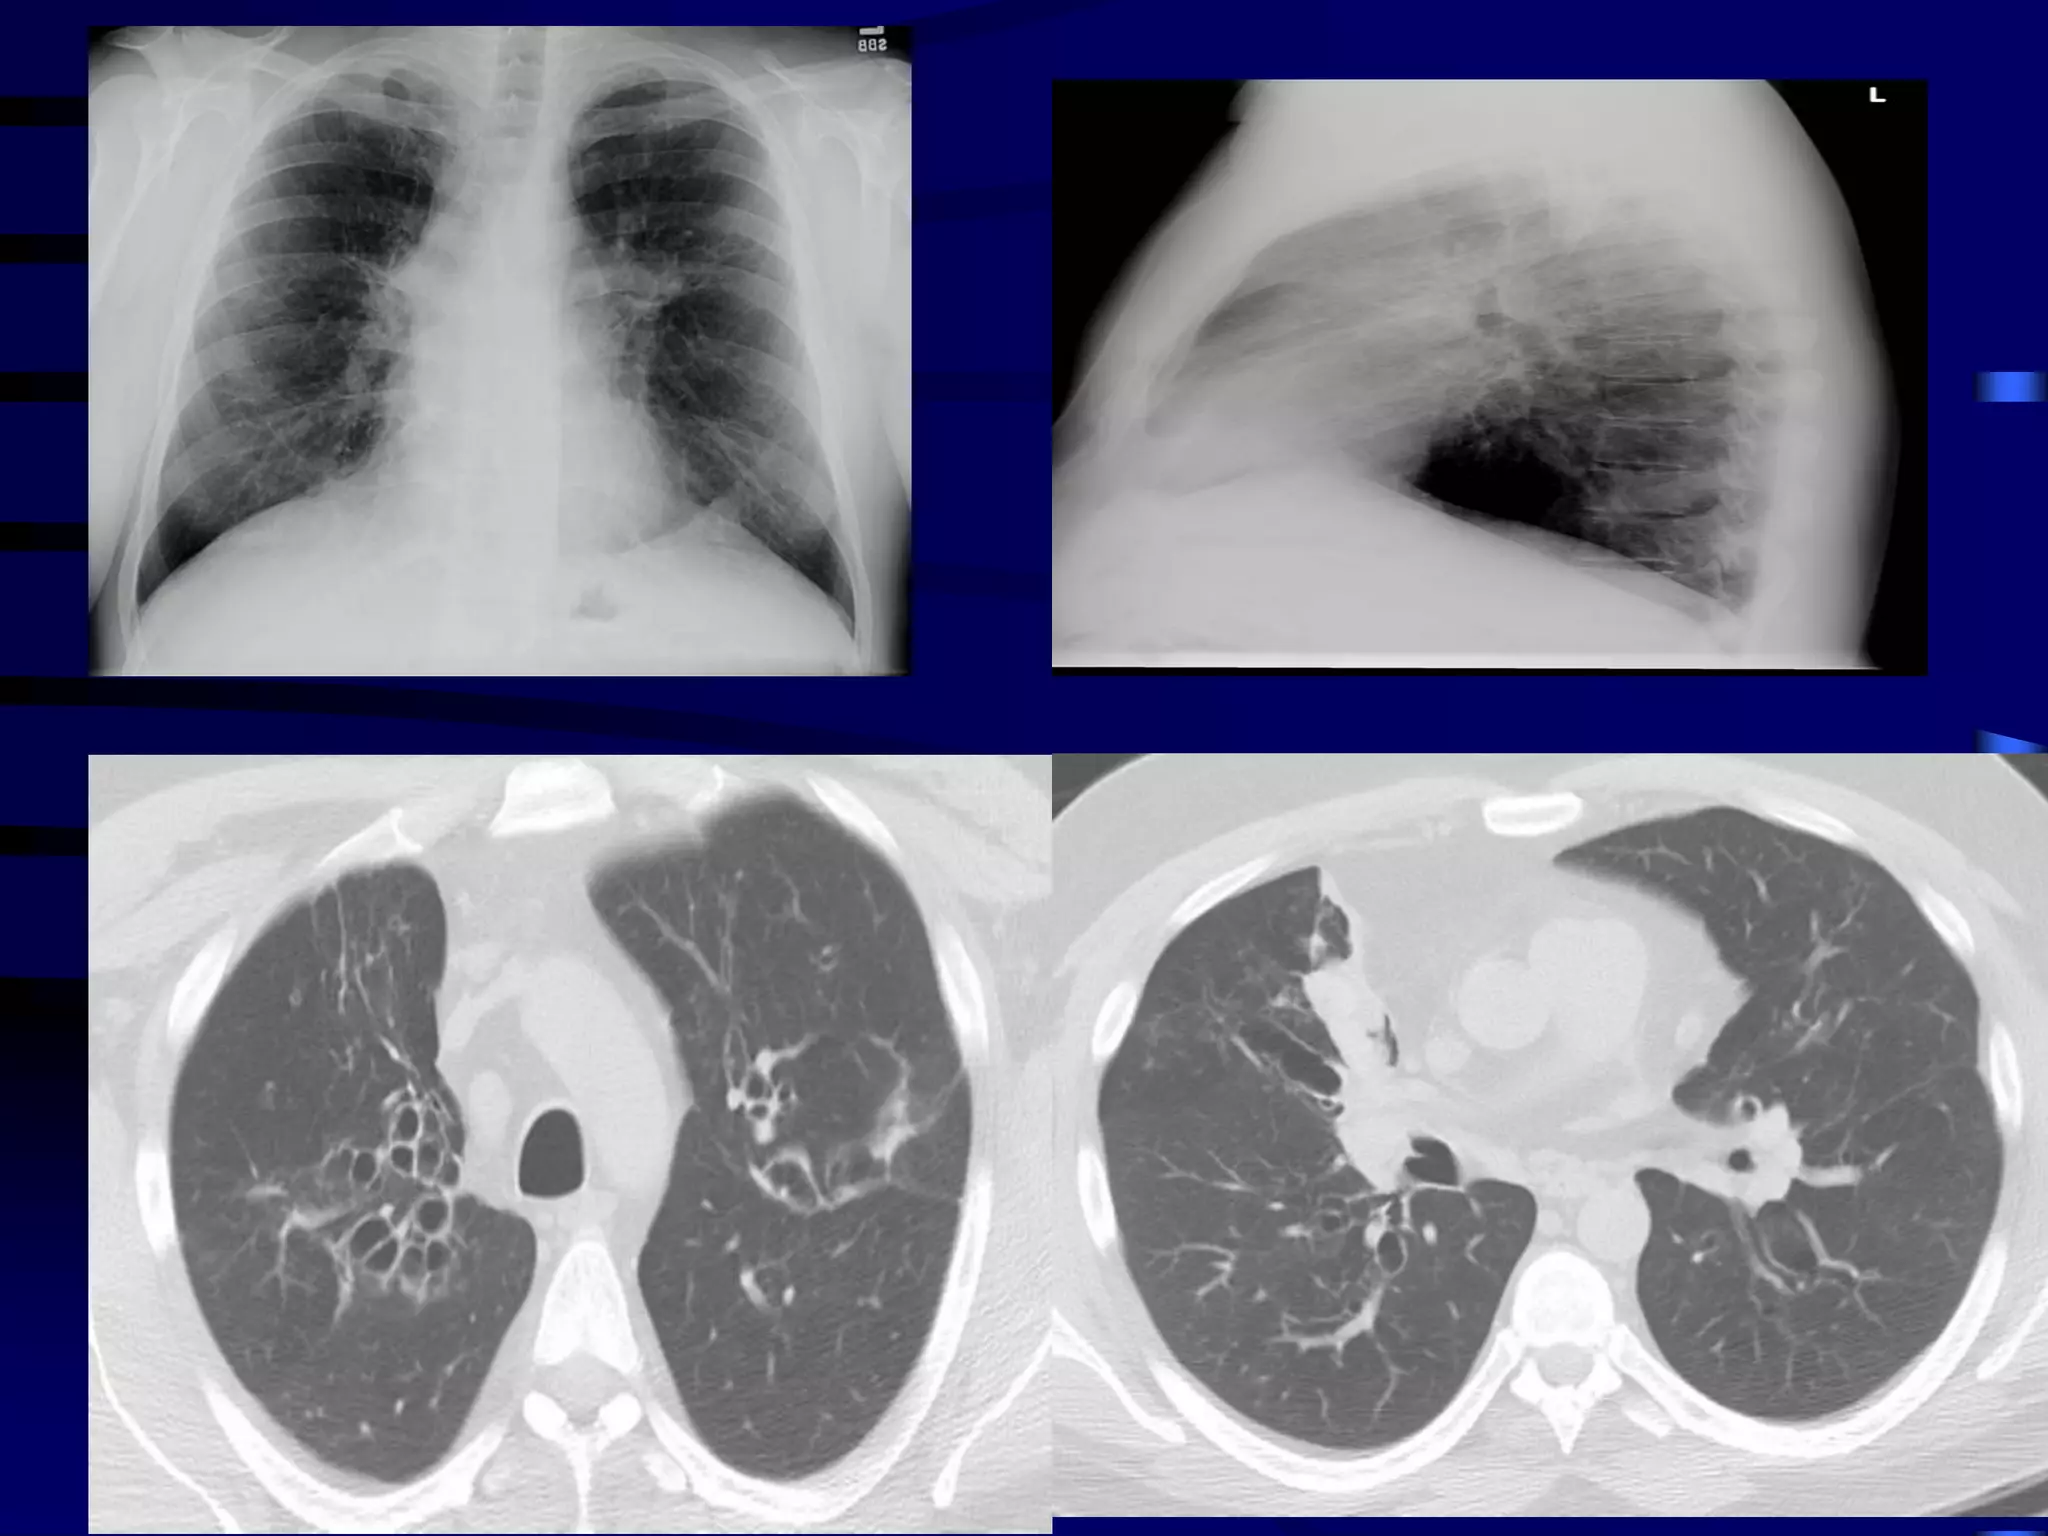

Chronic Wheezing

 Thriving child – Happy wheezer

 Child failing to thrive - Causes

Exclude other conditions

 Structural problems: bronchoscopy

 URTD : Polysomnography,

 Esophageal disease: Barium swallow, pH

probes, scopes and gram

 Primary ciliary dyskinesia: nasal ciliary motility,

Exhaled NO, EM, saccharine test

 TB: mantoux, induced sputum/ gastric lavage/

BAL = Culture, microscopy & PCR

 Bronchiectasis: HRCT scan, BAL

 CF: sweat test, nasal potentials, genotypes

 Systemic immune deficiency: Ig subtypes,

lymphocytes & neutrophil function, HIV

 Cardiovascular disease: echo, angiography